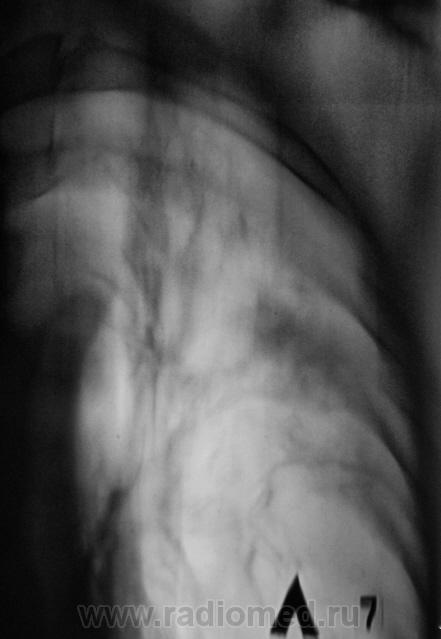

Я не очень хорошо разбираюсь в линейных томограмаах, но мне кажется что есть полости с обеих сторон, а это - показатель активности процесса.

Для доствоерности бы сделал КТ - если есть полости деструкции или "дерево-в -почках" - определенно активный процесс. (даже если не получено БК в мокроте). Можно тогда будет прицельно дать зону  с какой брать ПВБ.

На мой взгляд, полости есть.

КТ - нет.